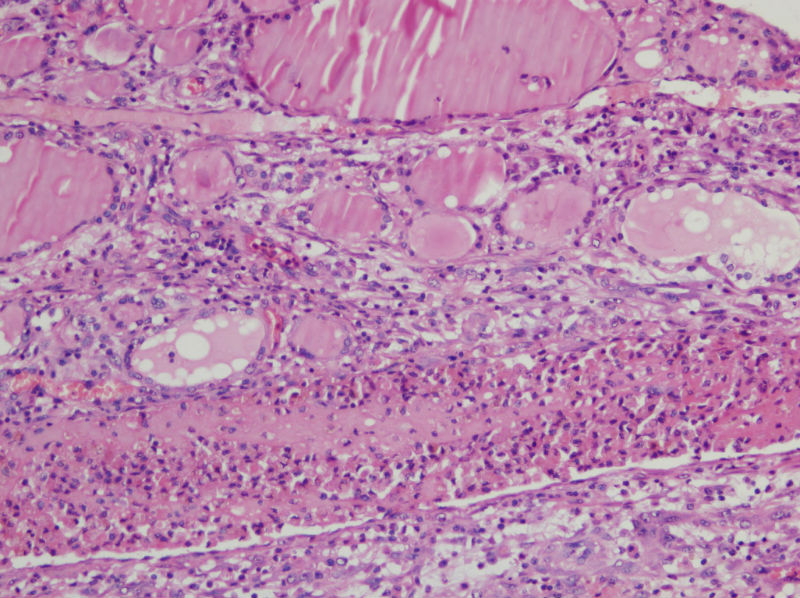

甲状腺囊肿,请老师们指教

男,44,甲状腺囊肿.直径1.5公分,内流清亮液

结节性甲状腺肿伴出血、囊性变。囊肿边上的滤泡大小不一,纤维组织增生,还可见炎细胞浸润。

结节性甲状腺肿伴囊性变。图2右上角的滤泡上皮似乎有些嗜酸性变。总之:良性病变。图13伴有出血。

结节性甲状腺肿伴囊性变     还可见囊壁周围伴有感染吧。